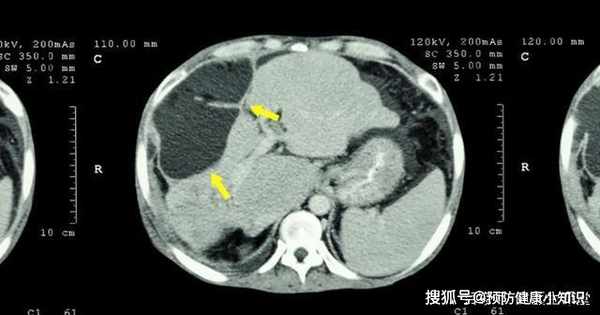

拿到結果後,劉女士崩潰大哭,甲胎蛋白485ug/L,確診肝癌。